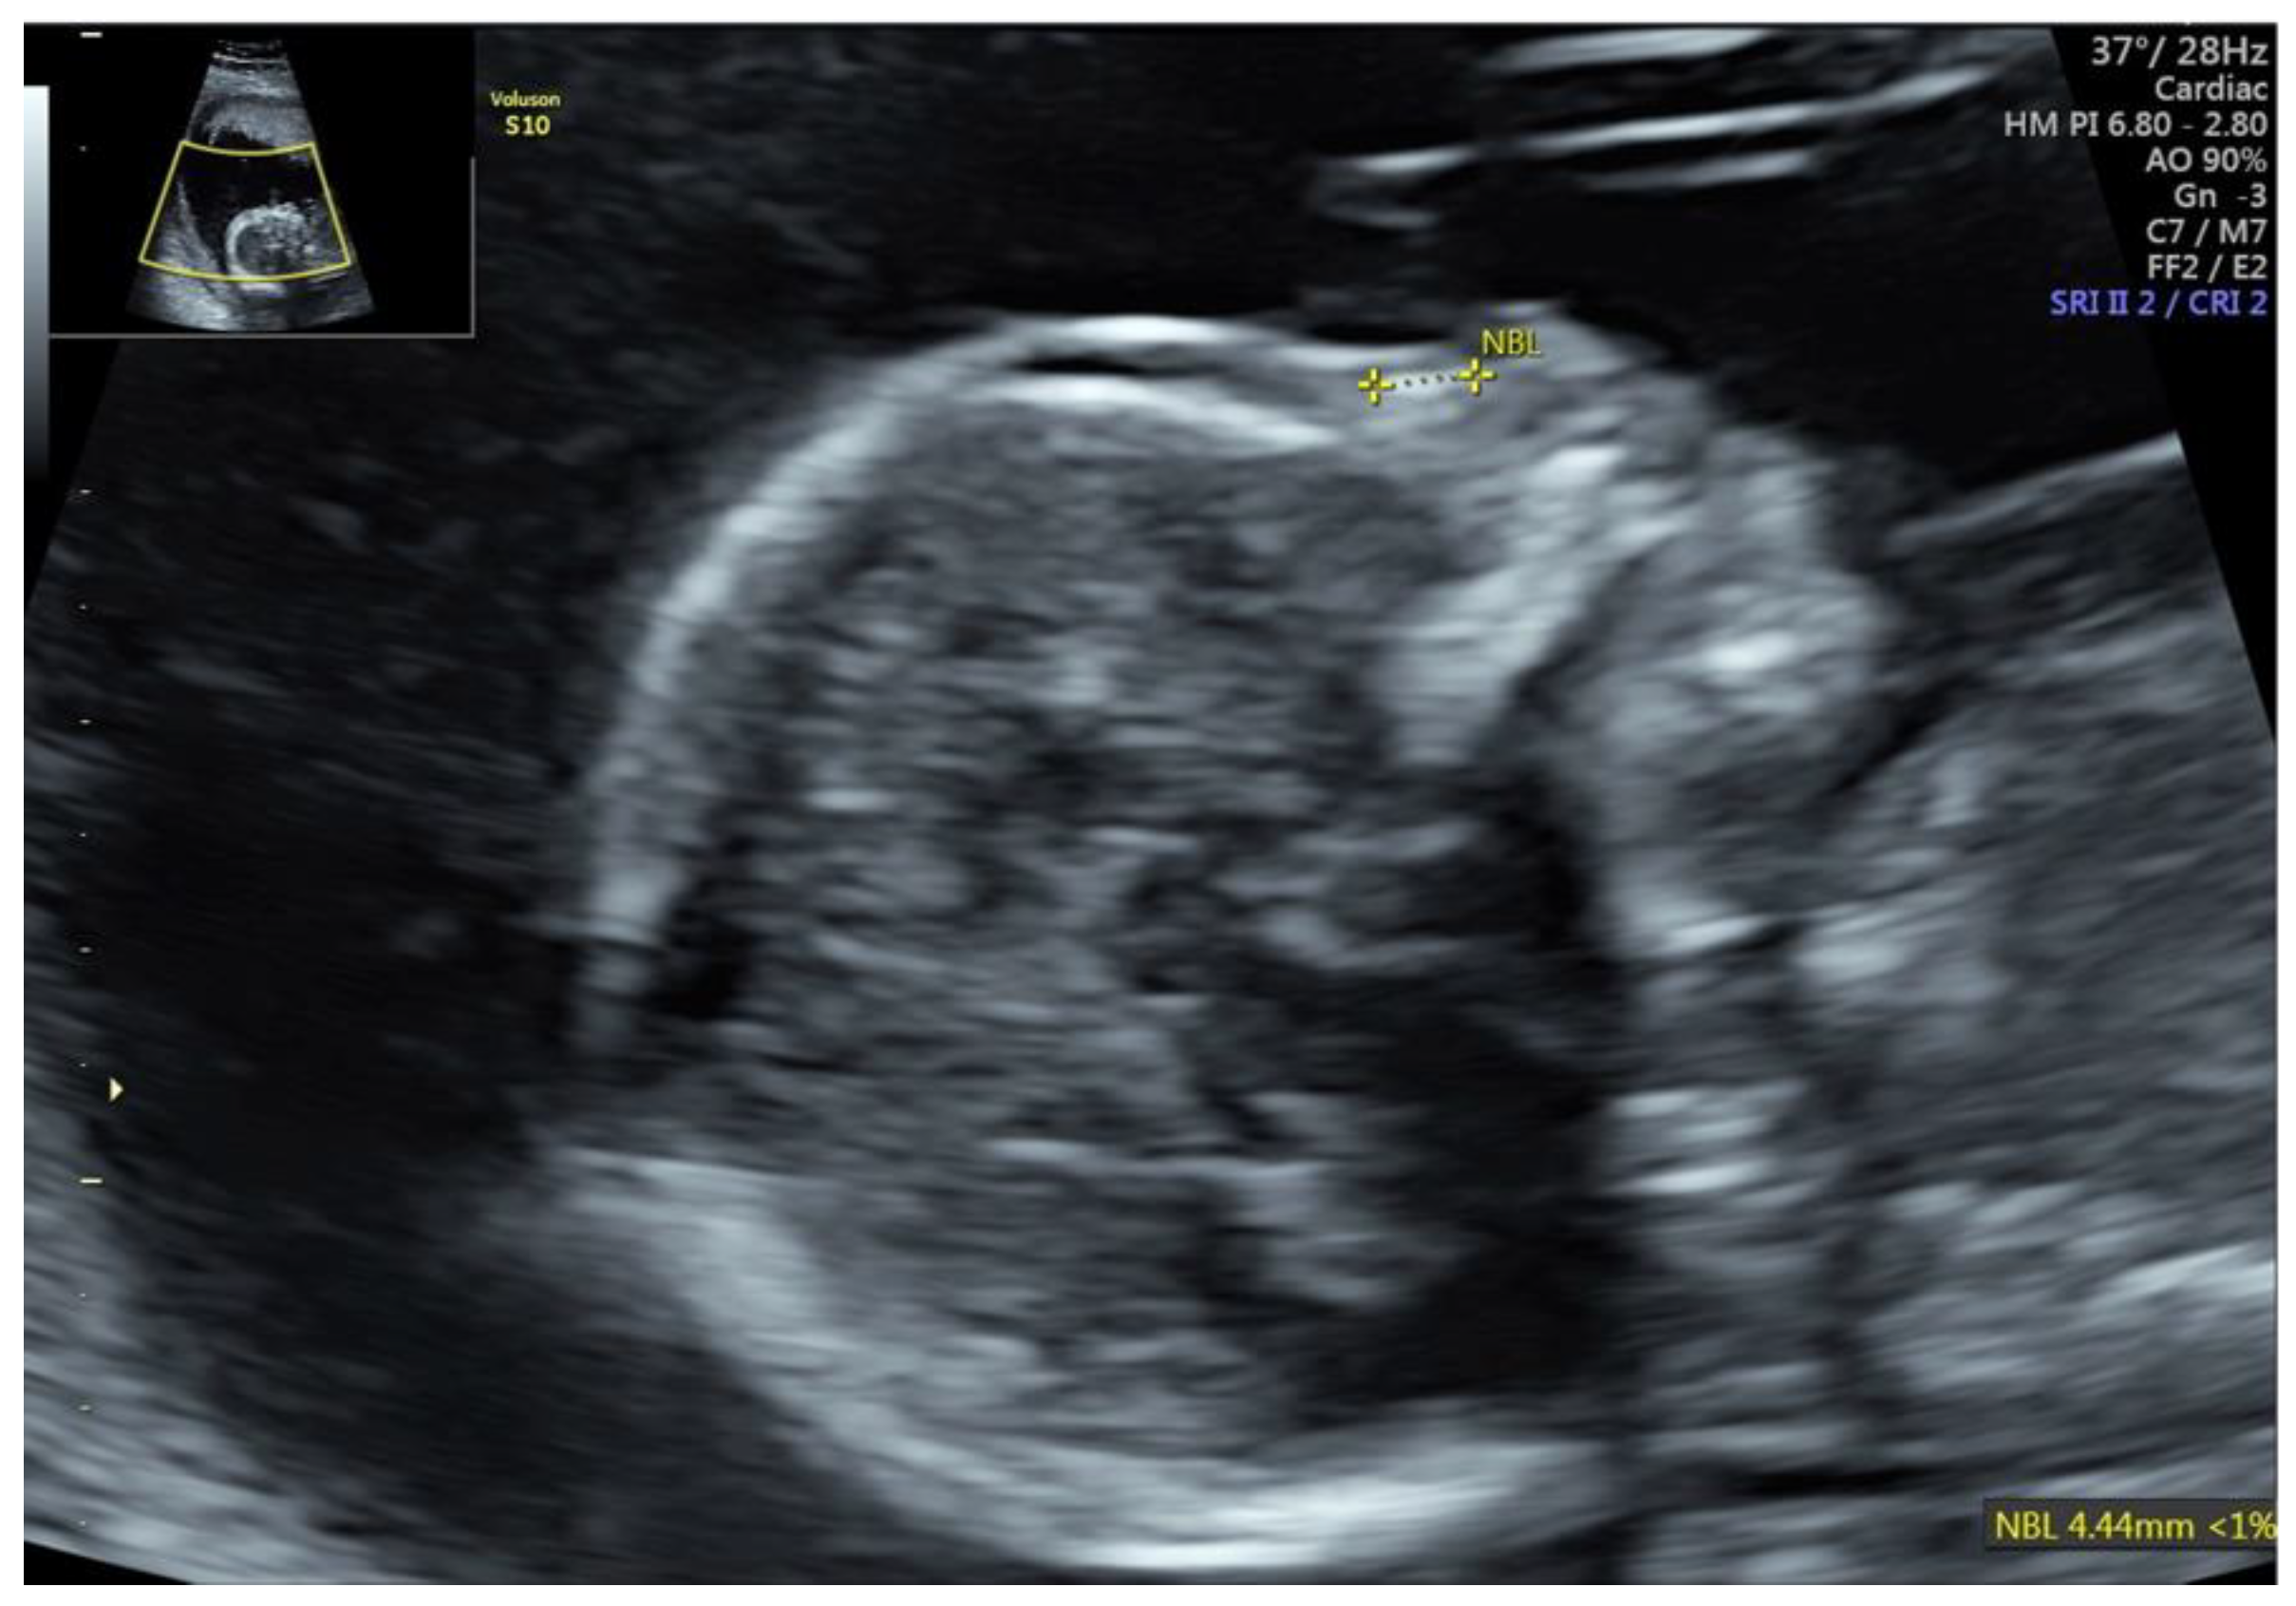

Fetal Nasal Bone Hypoplasia in the Second Trimester as a Marker of Multiple Genetic Syndromes

Moczulska, H.; Serafin, M.; Wojda, K.; Borowiec, M.; Sieroszewski, P. Fetal Nasal Bone Hypoplasia in the Second Trimester as a Marker of Multiple Genetic Syndromes. J. Clin. Med. 2022, 11, 1513. https://doi.org/10.3390/jcm11061513